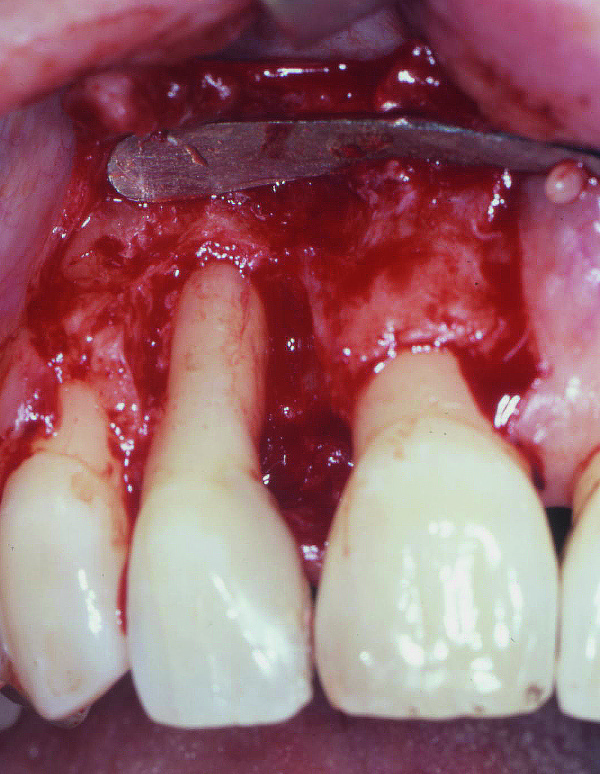

Rezektiv prosedurlar zamanı müəyyən miqdarda yumuşaq toxuma (diş əti), sərt toxuma (sümük) və ya kombinə olunmuş şəkildə (həm sümük, həm də yumuşaq toxuma) rezeksiya həyata keçirilir. Prosedur yerli ağrısızlaşdırma altında aparılır. Əməliyyatdan sonrakı dövrdə fərdi qulluq və gigiyena qaydalarının mötəxəssis tərəfindən izahı və müvafiq instruksiyanın verilməsi olduqca önəmlidir.